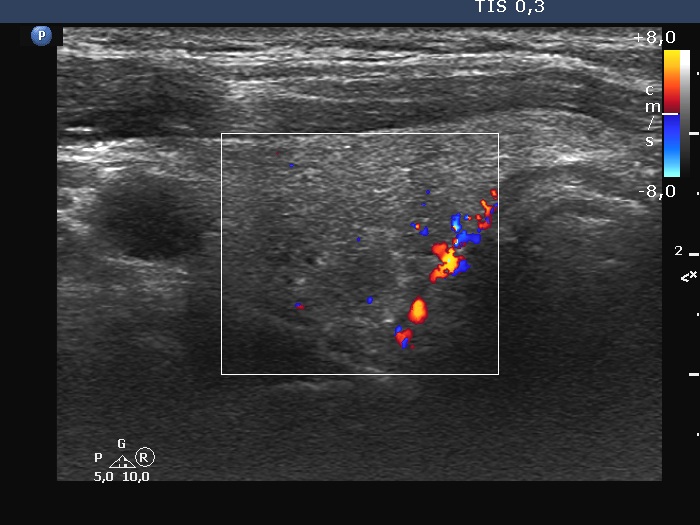

Right lobe, longitudinal scan

Right lobe, transverse scan, color Doppler mode. The vascularity is still decreased.